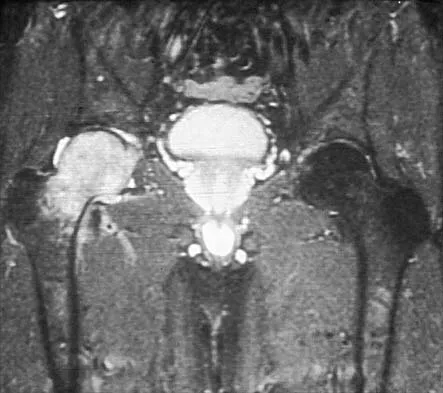

Figures 20a and 20b show the AP and lateral radiographs of a 62-year-old man who has had hip pain for the past 3 weeks. Figure 20c shows a CT scan of the abdomen and pelvis. A needle biopsy specimen is shown in Figure 20d. Preoperative management should include which of the following?